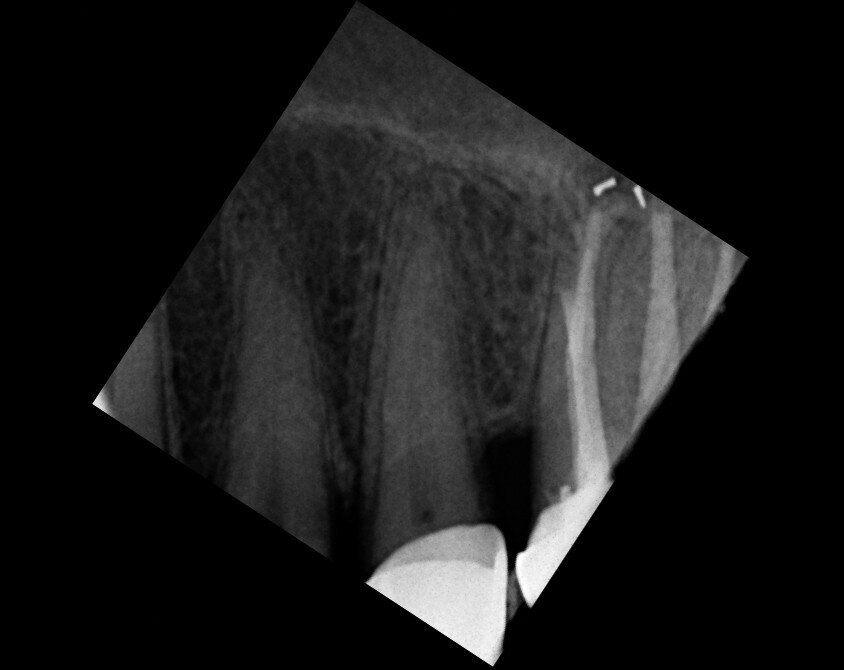

A patient was referred to the office with problems related to separated files. He was a pilot and was complaining of pus draining from his nose when flying. From the preoperative radiograph (Fig. 1), it was clear that there were two separated file fragments in the mesial canals and one cone passing beyond the apex in the palatal root. I requested an iCAT scan, and from this, the left sinus was clearly almost full with inflammatory fluid (Fig. 2) and the cone in the palatal canal was clearly emerging into the sinus. We could also see the two separated files in the two mesial canals clearly in the MPR view (Figs. 3 & 4), as well as another file entering the sinus and not attached to the canal (Fig. 5). We could see the file using different filters (Figs. 6–9), as well as the inflammation inside the sinus and the separated file. We additionally gained a better idea of the location of the cone protruding from the palatal canal into the sinus.

The treatment plan was to try to solve it with a conventional approach and if necessary to perform microsurgery to save the tooth. With the help of H-files, I managed to retrieve the cone from the palatal root, but the files inside the mesial root were impossible to bypass or even to reach with ultrasonic tips. I decided not to overdo it in order to avoid creating an additional problem, like perforating the canal, and decided to seal the canals (Fig. 10). A surgical approach was immediately taken for the mesial canals, cutting 3 mm of the mesial root using the Impact Air handpiece (SybronEndo), and this gave me a direct view of the Schneiderian membrane, where the third file was barely hanging (Figs. 11 & 12). I managed to delicate grab it and to remove it (Fig. 13). Figure 14 shows the postoperative situation, after performing retrograde preparation of the mesial canals.